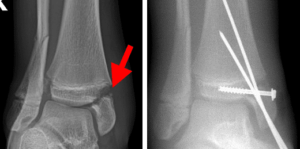

Understanding Ankle Fractures in Children

In children and adolescents, ankle fractures typically affect the tibia or fibula, often involving the growth plates—specialized areas of cartilage near the ends of long bones. Growth plates play a critical role in bone development, gradually hardening into solid bone as the child matures. However, because these growth plates are the last parts of the bones to solidify, they are particularly prone to injury and fractures.

As adolescents approach the end of their growth phase, growth plates begin to close and harden, making them susceptible to transitional fractures during this maturing stage. Two common types of transitional ankle fractures are triplane fractures and Tillaux fractures, which require specific treatment approaches depending on their severity and location (refer to the Treatment section for more details)